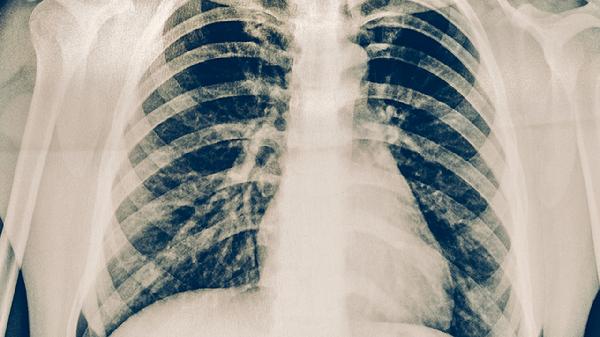

需重新进行痰涂片抗酸染色检查,必要时做结核分枝杆菌培养及药敏试验。检查前应深咳获取下呼吸道痰液标本,连续送检可提高检出率。若发现耐药菌株需及时调整抗结核方案。

出现持续低烧伴盗汗、消瘦时需住院完善胸部CT、血沉等检查。住院期间监测肝肾功能,警惕药物性肝炎发生。重症患者可能需要静脉滴注链霉素注射液,并进行营养支持治疗。